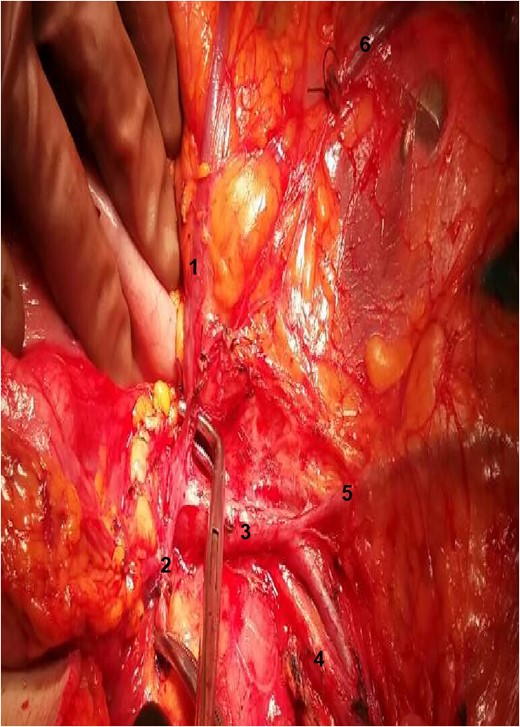

The relation between the vessels: 1: gastroepiploic artery; 2: RCA; 3: superior mesenteric vein; 4: SMA.

During the operation, surgeons attained to isolate the main supplying arteries of the right colon and their origins. The ileocolic and the middle colic arteries were observed, as typically, emerging as isolated vessels from the superior mesenteric artery (SMA). However, the origin of the RCA was nor observed from the SMA, nor from the previous arterial branches, as in common. Surgeons continued ascending dissection in order to detect the origin of the RCA that was finally observed arising from the right gastroepiploic artery (Figs 1–2). Pericolic lymph nodes and the lymph nodes that followed the central wards of the ileocolic, the middle colic and the aberrant RCA were gently dissected. The operation continued in the usual pattern. A drainage was placed and was finally removed the 6th postoperative day. The patient was discharged the 10th postoperative day with instructions. At the follow-up, the 14th postoperative day, the patient suffered no complications whatsoever.